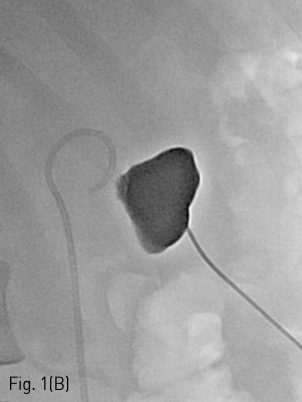

환자는 왼쪽 신장의 isolated calyx에는 8.5Fr. drainage catheter가 insertion 되어 있고 left renal pelvis에는 double J stent가 insertion 되어 있는 상태로 prone position을 취하였다. 기존의 drainage catheter에 0.035inch 유도 철사(Terumo, Tokyo, Japan)를 insertion 하고 catheter는 제거한 후 8Fr. Sheath(Boson, Shrewsbury, USA)를 삽입하였다. 조영제(Visipaque, GE healthcare, Chicago, USA)를 주사하여 tubogram을 시행하였고 isolated calyx 와 콩팥깔때기와의 연결성은 없었다. (Fig.1B) 초음파 유도 하에 21G 천자바늘(Cook, Bloomington, USA)로 isolated calyx를 천자하고 X선 투시하에 천자바늘을 콩팥깔때기에 insertion 되어 있는 double J catheter를 향해 진입시켰다. (Fig. 2A, B) 천자바늘의 속심을 제거한 후 X선 투시하에 조영제를 주사하여 isolated calyx를 지나 콩팥깔때기가 천자된 것을 확인하고 0.018inch 유도 철사(A & A, Gyeonggi, Korea)를 넣었다. (Fig. 2C) 이후 천자바늘을 제거하고 단일 막대 접근 장치(yellow sheath; A & A, Gyeonggi, Korea)를 이용하여 접근로를 확보했다. 유도 철사와 metal stiffening inner cannula를 제거하고 0.035inch 유도철사(Terumo, Tokyo, Japan)를 넣고 6mm x 4cm balloon(Boson, Shrewsbury, USA)을 이용하여 isolated calyx와 콩팥깔때기 간 neoinfundibulum 을 재건하였다. (Fig. 2D) 삽입되어 있는 유도 철사를 통해 isolated calyx, neoinfundibulum 그리고 콩팥깔때기를 차례로 통과하도록 10.2Fr. nephrostomy catheter(Cook, Bloomington, USA)를 위치시켰다. (Fig. 2E) 4일 후 기존의 10.2Fr PCN catheter insertion site를 통하여 10Fr sheath(Terumo, Tokyo, Japan)를 insertion 한 뒤 0.035inch 유도철사(Terumo, Tokyo, Japan)를 방광까지 진입시킨 뒤, 26cm 7Fr double J stent(Boson, Shrewsbury, USA)의 원위부는 방광에 위치시키고 근위부는 isolated calyx에 위치시켰다.(Fig. 3) 이후 isolated calyx로의 접근로에는 10.2Fr. nephrostomy catheter(Cook, Bloomington, USA)를 삽입하고 시술을 종료했다.

Fig 1B

(B) Tubogram did not show a connection between the isolated calyx and the renal pelvis.